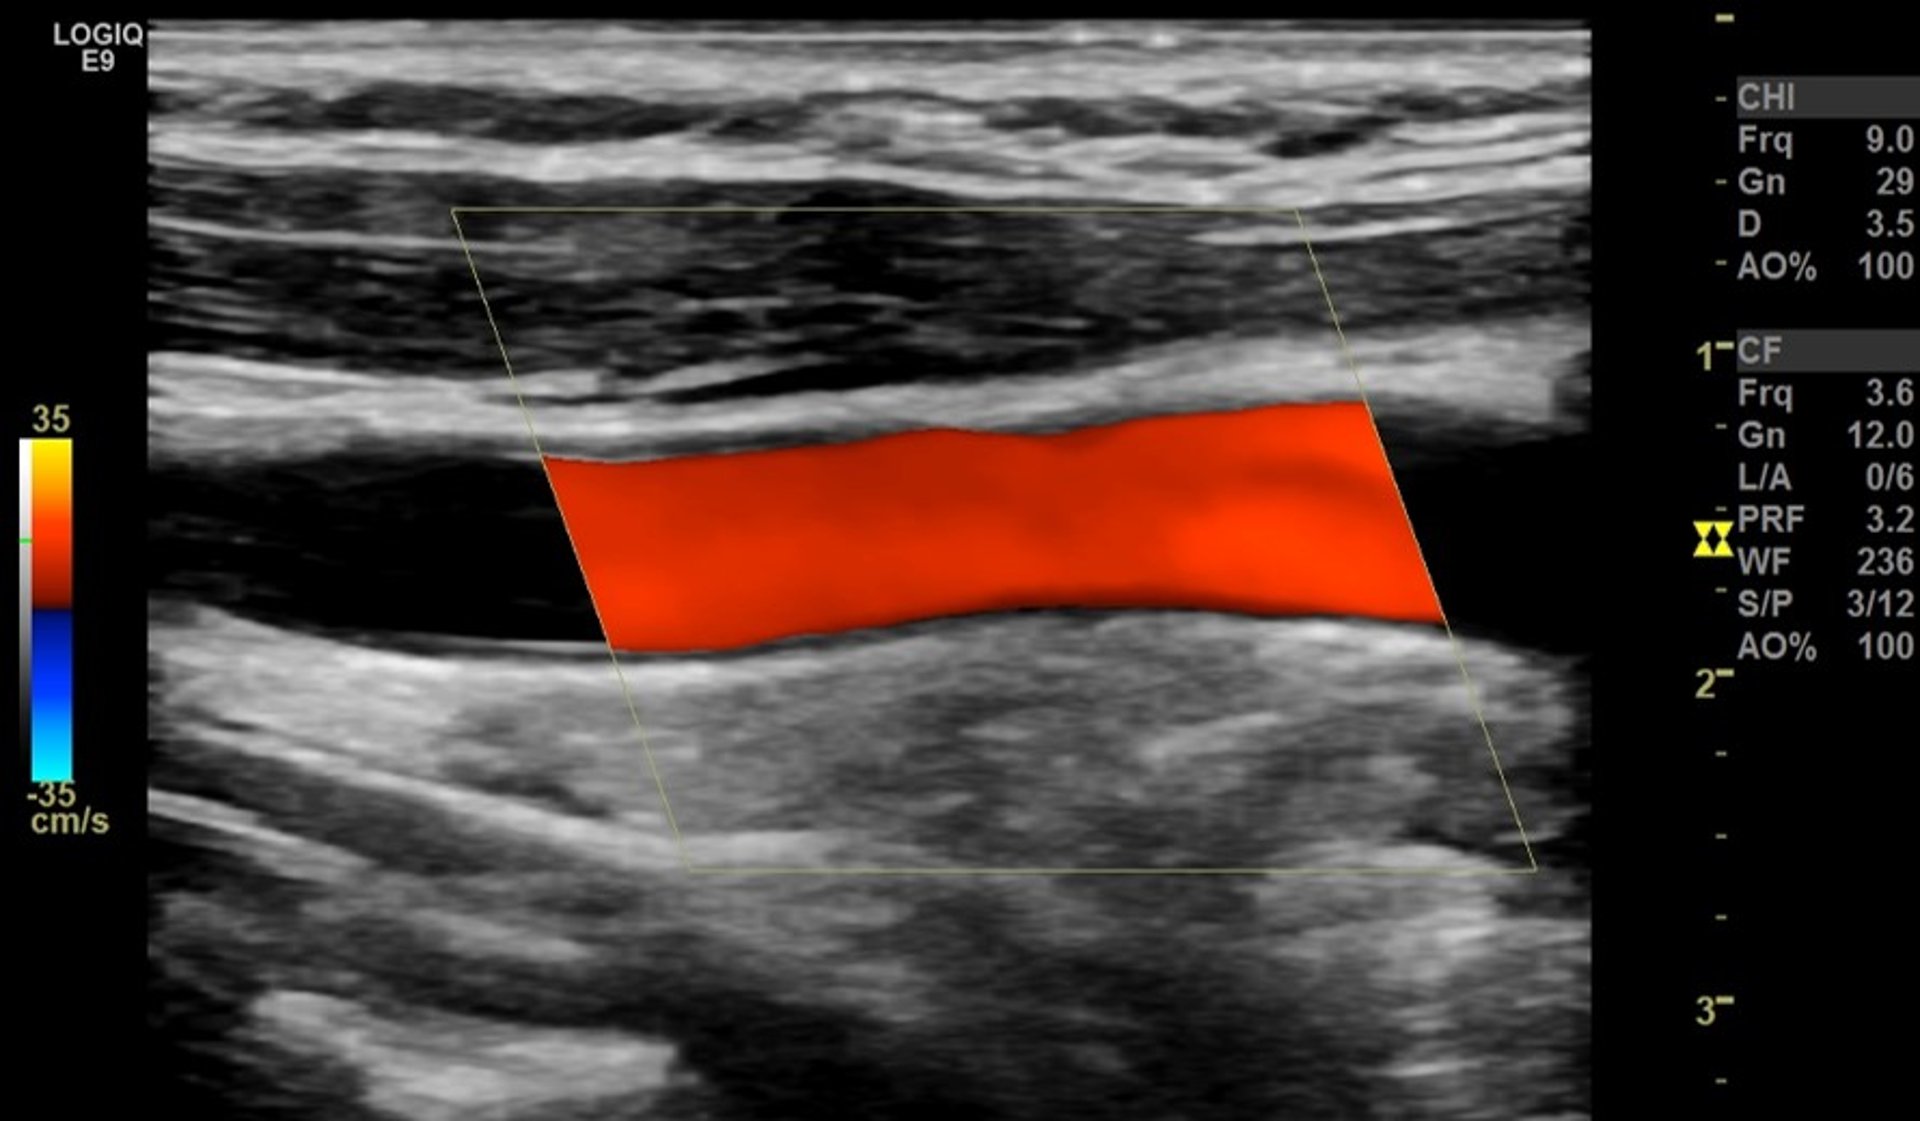

Farbdoppler-Ultraschall

Beim Farbdoppler-Ultraschall werden die Grauschattierungen der mittels Doppler-Sonographie erstellten Aufnahmen vom Blutfluss farblich überlagert. Die Farbe markiert die Richtung des Blutflusses. Rot kann zum Beispiel den Fluss zum Schallkopf hin anzeigen, während blau zur Anzeige des Flusses vom Schallkopf weg verwendet wird. Die Helligkeit der Farbe zeigt an, wie schnell das Blut fließt.

Mittels Farbdoppler-Ultraschall lässt sich das Schlaganfallrisiko beurteilen, da damit Verengungen oder Blockaden von Hals- und Hirnarterien leichter festgestellt und beurteilt werden können. Das Verfahren eignet sich zur Untersuchung von Patienten mit transitorischer ischämischer Attacke oder Schlaganfall sowie von Patienten, die Risikofaktoren für eine Atherosklerose, aber keine Symptome haben. Der Farbdoppler-Ultraschall wird auch zur Beurteilung des Blutflusses zu inneren Organen und Tumoren angewendet.